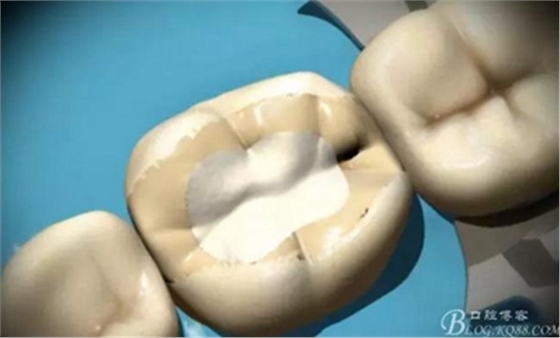

綠標平頭錐形金剛砂牙合面牙體預(yù)備

預(yù)備要求

綠標平頭錐形金剛砂鄰面牙體預(yù)備